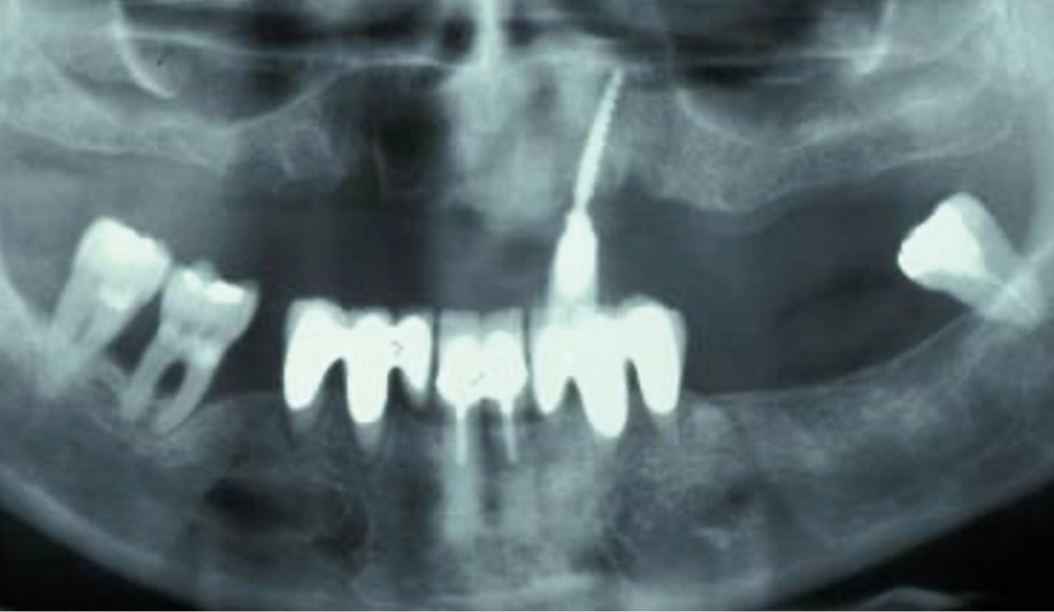

Peri-implant mucositis can be defined as an inflammatory lesion of the soft tissues (mucosa) surrounding the dental implant. Peri-implantitis is an inflammatory lesion of the mucosa affecting the supporting bone (crestal bone) with crestal bone loss and loss of osseointegration. Derks et al. report a prevalence of 43% for peri-implant mucositis and Jepsen et al. estimate that the prevalence of peri-implantitis could reach 22% (Figs. 1, 2).2,3 Peri-implantitis is usually accompanied by crestal bone loss (Fig. 3) and soft tissue changes in the peri-implant sulcus, which can be diagnosed by an increase in bleeding on probing (BOP) more than 5mm over previous examinations and/or suppuration8 (Fig. 4). Also excess of residual cement might contribute to crestal bone loss (Fig. 5).7

The underlying inflammatory processes are still not completely understood. However, increasing evidence shows that the host and the peri-implant conditions might play a pivotal role in the development of peri-implantitis (Figs. 1, 2).2,3

Oral biofilm, oral hygiene, poorly controlled diabetes, smoking and peri-implant plaque have been identified as independent risk factors enabling the development and progression of peri-implantitis. Also, the routinely usage of screw-retained implant-supported restorations seem to be associated with a higher prevalence of peri-implantitis. Having said that, the exact etiology remains often unknown.4-6 And patients with titanium implants and with a good oral hygiene can also develop peri-implantitis.5